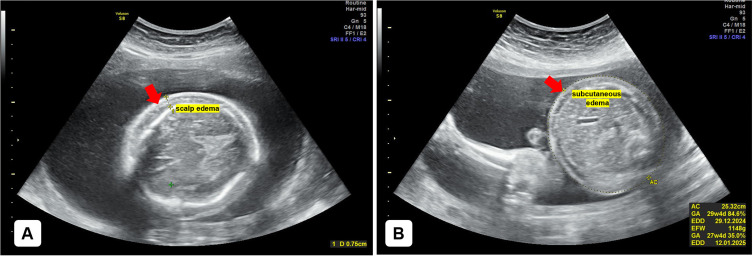

Case illustration: A woman in her early 30s presented to the emergency department with the chief complaint of not feeling fetal movements for one day prior to admission. This was her fourth pregnancy, with no history of miscarriage or abortion. The patient reported a history of regular smoking (two packs per day) and frequent alcohol consumption. Her vital signs were unremarkable upon admission. The baby was delivered weighing 1755 grams and measuring 44 cm, with grade 2 maceration and no signs of life. Physical findings, including fluid accumulation in the chest and body, led to a pediatric diagnosis of hydrops fetalis.